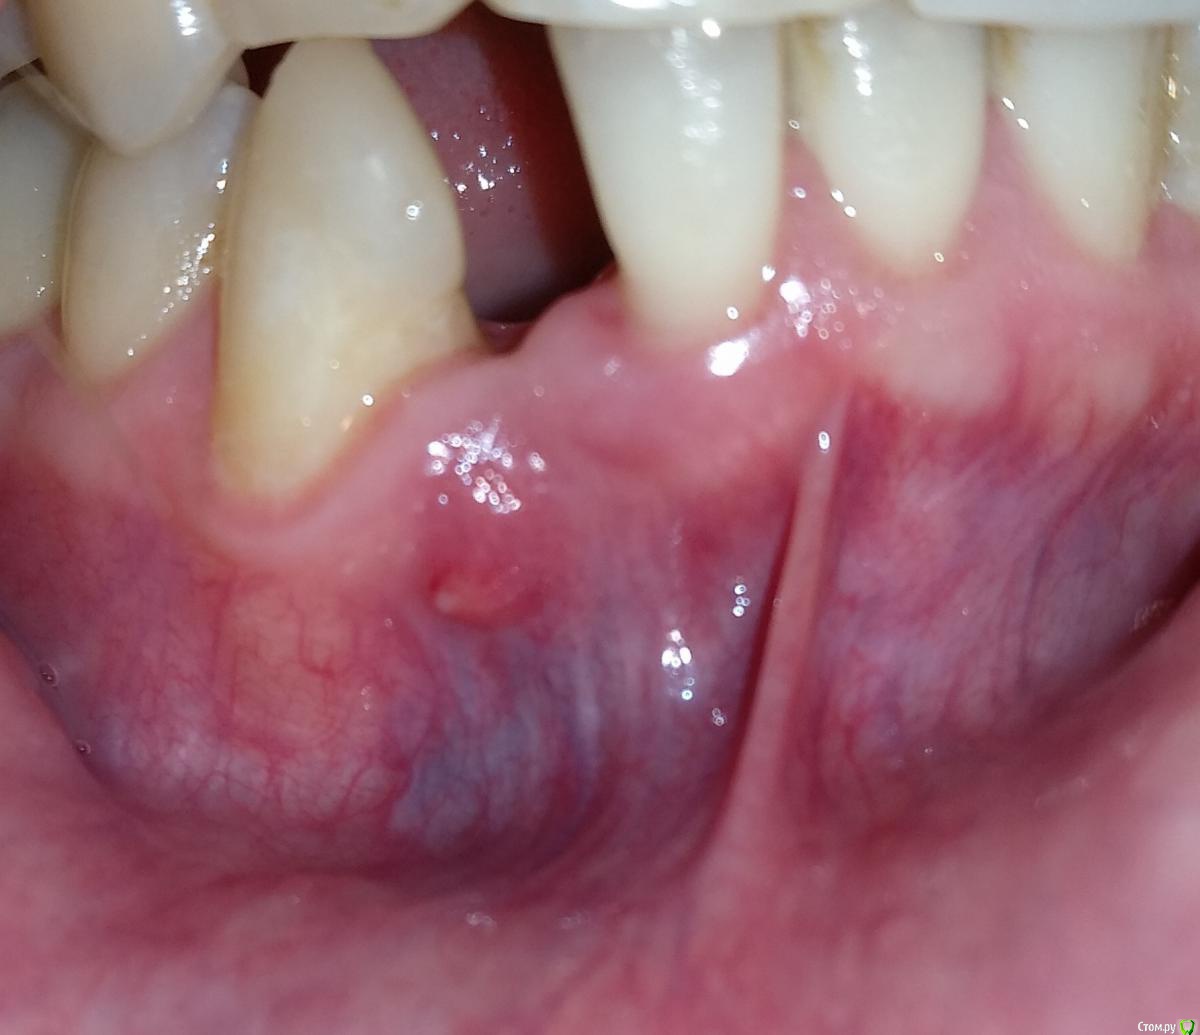

Medbrat Опубликовано 5 ноября, 2019 Поделиться Опубликовано 5 ноября, 2019 Здравствуйте, уважаемые доктора!Прошу консультации по следующему случаю:Три недели назад была удалена правая двойка снизу. Через 4 дня альвостаз выпал из лунки, на пятый день альвеолит (боль, лимфоузлы. Метрогил). Доктор при осмотре сказал само пройдёт. Через две недели на осмотре Rg - чисто. Сказал не беда, лучше не трогать, если что - выйдет на переднюю стенку, тут всё рядом. В итоге: прошло три недели, на передней стороне десны небольшой свищ, небольшое гнойное/кровяное отделяемое в течении недели.Выглядит прилично, не беспокоит. Подвывих рядом стоящей единицы (не фиксировали) тоже неплохо, рот уже закрывается нормально.Вопрос, что же делать с альвеолитом - само пройдёт?Спасибо! Ссылка на комментарий

Medbrat Опубликовано 5 ноября, 2019 Автор Поделиться Опубликовано 5 ноября, 2019 Прошу прощения, вот фото. Ссылка на комментарий